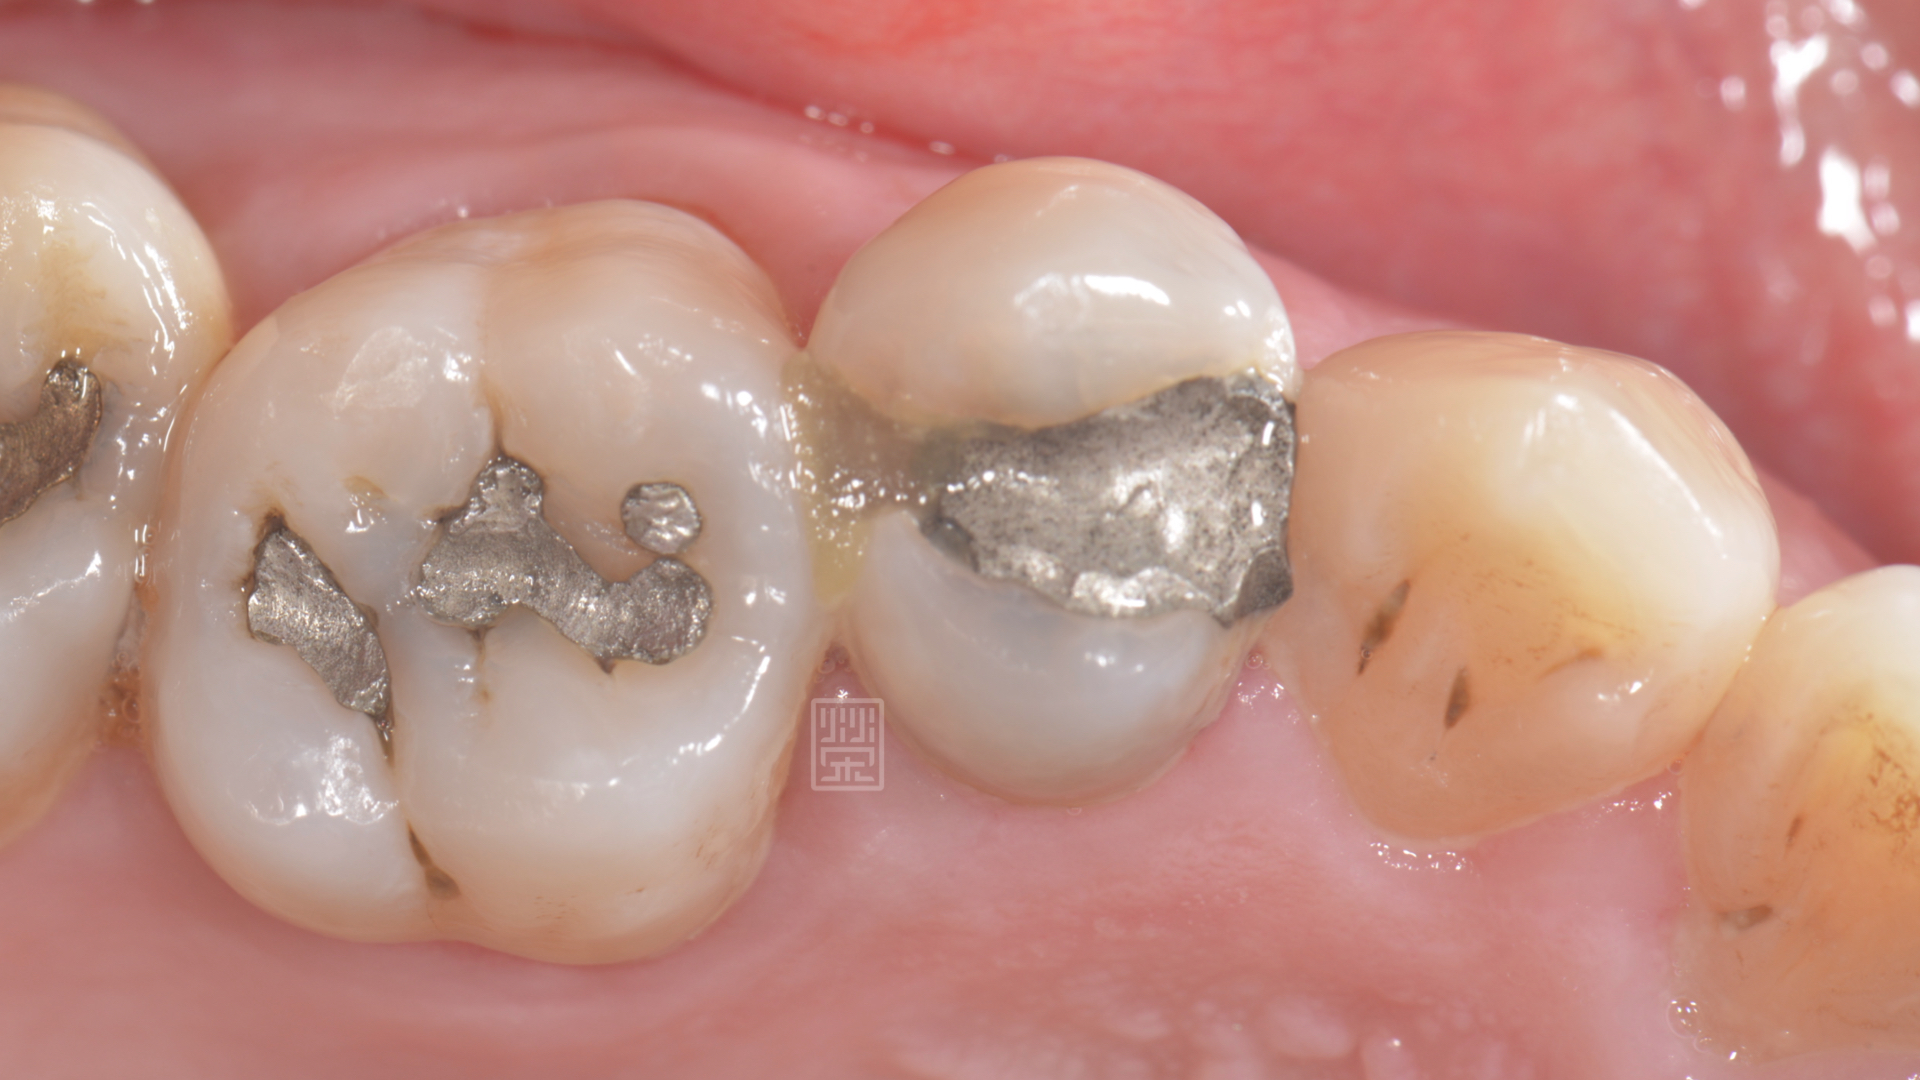

黃先生覺得牙齒常常會卡東西,以為是以前補的地方掉了,榮醫師檢查後發現,不是填補物掉了,而是有新的蛀牙。

小臼齒齒縫間有個小洞,很容易塞食物

X光檢查下,雖然咬合面的蛀洞小,但是下方有很嚴重的蛀牙